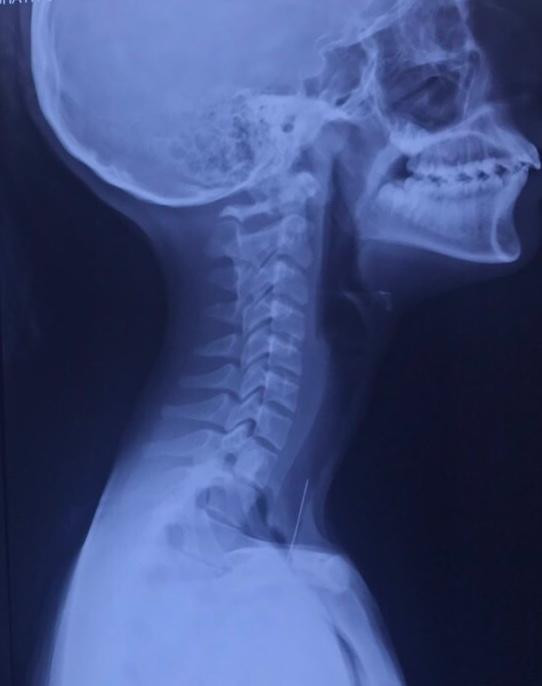

މި މަހުގެ 23 ވަނަ ދުވަހު މިފަދަ ހިތާމަވެރި ހާދިސާއެއް ވަނީ ހިނގާފައެވެ. އުމުރުން 14 އަހަރުގެ އަންހެން ކުއްޖެއްގެ ކަރު ތެރޭގައި ޕިން ތާށިވުމުގެ ސަބަބުން ވަނީ އޮޕަރޭޝަނެއް ކުރަންޖެހިފައެވެ. ބުރުގާ އެޅުމުގެ ތެރޭގައި ދެ ދަތް ދޭތެރެއަށް ޕިނެއް ލައްވައިގެން އުޅެނިކޮށް، ކޮށިއެރުމުން ޕިން ކަރު ތެރެއަށް ދިޔައީއެވެ. އެ ޕިން ނެގީ އައިޖީއެމްއެޗްގައި "ބްރޮންކޮސްކޮޕީ" އެއް ހަދައިގެންނެވެ.

ޑރ. ނަޒްމީ އަބްދުއްލަތީފް ވިދާޅުވީ ޒުވާން އަންހެންކުއްޖާގެ ކަރުތެރެއަށް ދިޔަ ޕިން ވޯކަލް ކޯޑާއި ކައިރީގައި ހުރުމުގެ ސަބަބުން ނަގަން ތަންކޮޅެއް ފަސޭހަވި ކަމަށެވެ. މި ހާދިސާގައި ޕިން ނަގަން ފަސޭހަވި ނަމަވެސް ހުރިހާ ފަަހަރަކު މި ގޮތަށް ކަންތައް ނުހިނގާނެ ކަމަށް ޑޮކްޓަރު ވިދާޅުވިއެވެ. އަދި ޕިން އެތެރެއަށް ދިޔަ ނަމަ ނުރައްކާތެރި ހާދިސާއެއް ހިނގުމުގެ ފުރުސަތު އޮތް ކަމަށް ވެސް ޑޮކްޓަރު ވިދާޅުވިއެވެ.